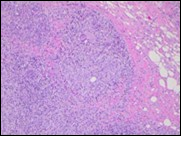

Figure 4.Granulomatous mastitis with epitheloid cell granuloma, langhans and foreign body giant cells with lymphocytic rimming12.

Core needle biopsy of idiopathic granulomatous mastitis enunciates multiple aggregates of non- caseating epitheloid cell granulomas within and encompassing breast lobules, constituted of epitheloid histiocytes, lymphocytes, neutrophils and multinucleated giant cells. Granulomatous inflammation is predominantly lobulo-centric. The inflammation is preponderantly composed of lymphocytes, plasma cells, epitheloid histiocytes, multinucleated giant cells and neutrophils. Neutrophils can configure micro-abscesses and encompass vacant micro-cystic cavities, morphological features which are in common with cystic neutrophilic granulomatous mastitis. Non specific lobulitis along with a lymphoid and plasma cell infiltrate accompanies the granulomatous inflammation. Necrosis is usually absent. Neutrophilic micro-abscesses can be accompanied by fistula formation 4, 5.

Multinucleated giant cells are detected in an estimated three fourths (78.5%) instances. Plasma cells are discernible in around half (53.9%) of the subjects and usually appear at the margins of cystic vacuoles with centric accumulation of neutrophils within the granulomas.